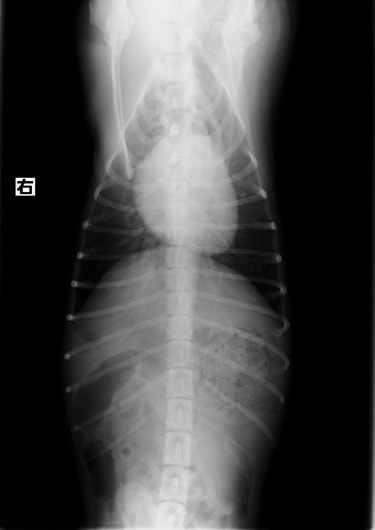

A:胸部レントゲン写真 正面像

左側胸壁よりLevine 4/6の連続性心雑音が聴取された。胸部レントゲン検査において心拡大が認められ、超音波検査においても肺動脈領域に連続的な異常血流が観察された。大学病院を紹介受診され、手術が行われた。現在はACE阻害薬のみの内服で補助的治療を行っている。